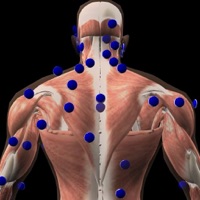

1. 'Gray's Anatomy', the renowned classic anatomical book by Henry Gray was first published in 1858 and is considered by many to be one of the most iconic and significant medical books of all time.

6. We recommend this app for Doctors, Nurses, Students, Teachers and anyone who is interested in the wonder and complexity of the human body.